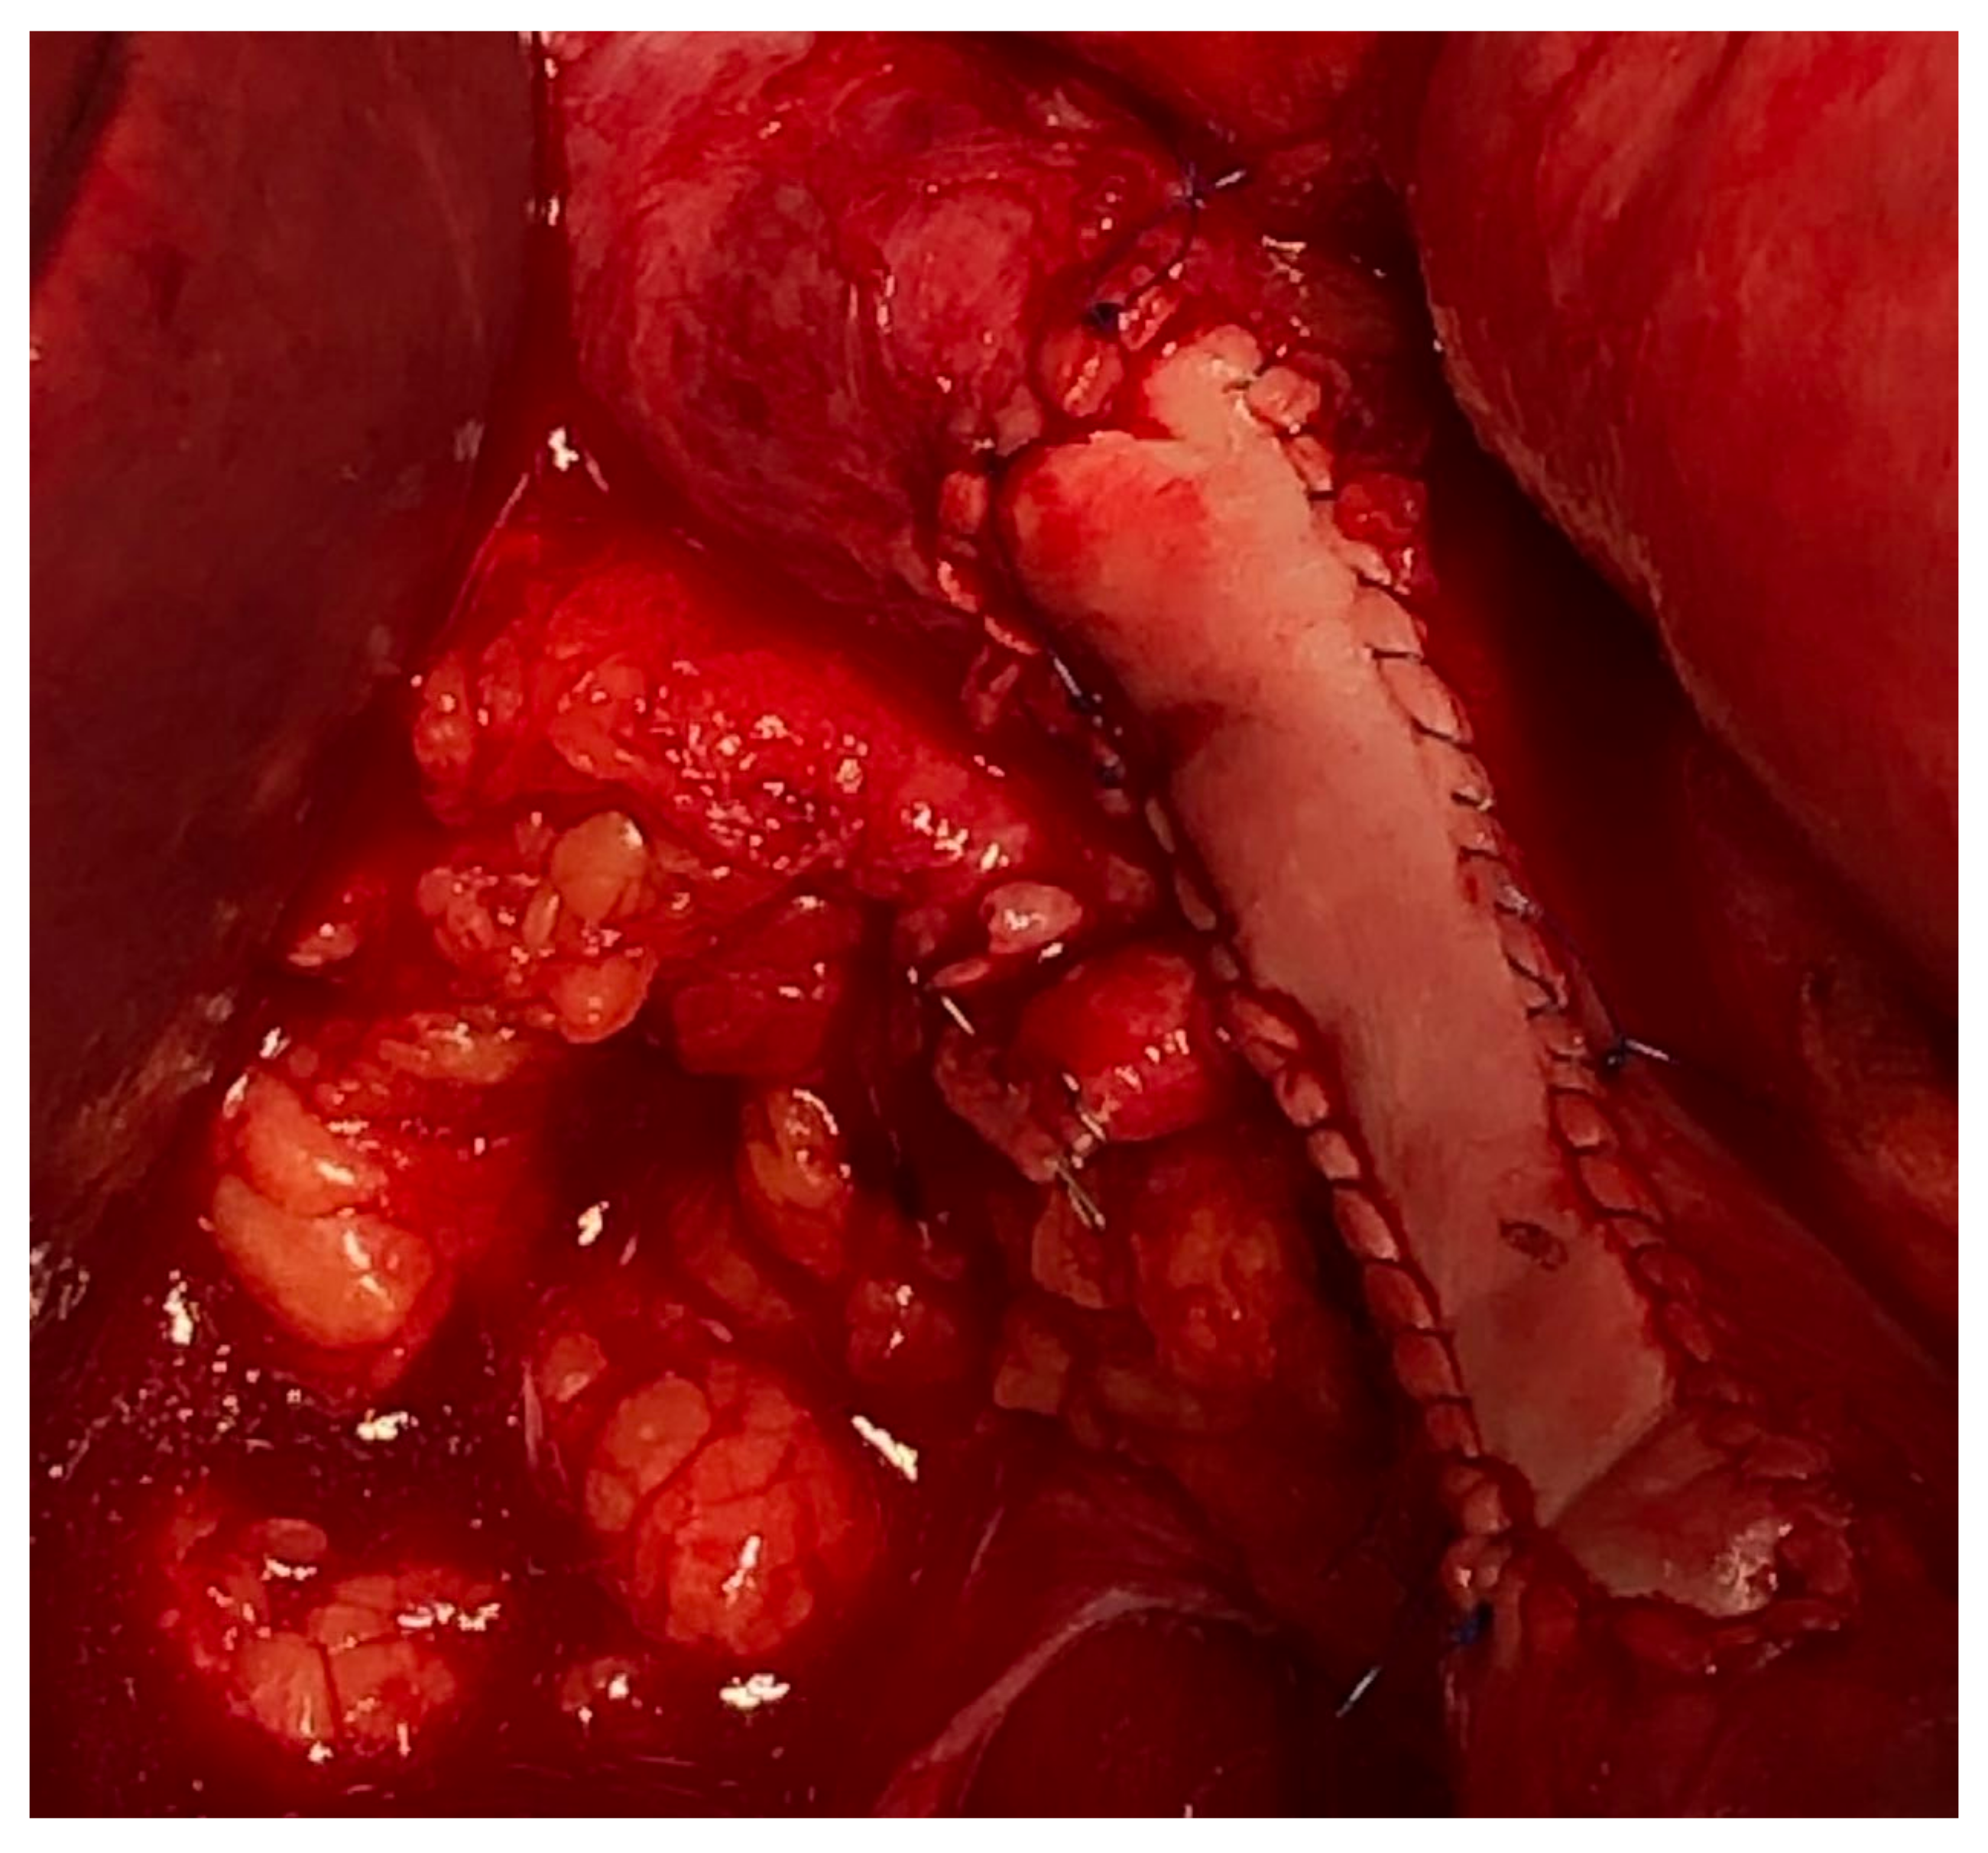

Management of the iliac vein follows similar dogmas as caval resections: patch repair, interposition graft, or ligation. The iliac vein is divided into two segments to plan reconstruction: segment I is defined between the origin of the external iliac vein and the internal iliac/hypogastric vein to the ilioinguinal ligament; segment II is defined by the common iliac vein per se. Reconstruction of the common or external iliac veins can be fashioned with an autologous left renal vein, contralateral femoral vein, cryopreserved cadaveric graft, or PTFE graft. Patency after reconstruction is lower compared to IVC reconstruction, favoring the use of PTFE with a 71% long-term patency [9] (Figure 4). When iliac vein resection includes the internal iliac inflow or hypogastric vein, this vein can simply be ligated.

Figure 4. Iliac artery and vein reconstruction after DD-LPS resection.